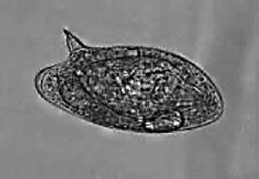

Observe, a seguir, a imagem de um ovo deste parasita, que pode ser identificado pela análise microscópica de fezes humanas. Qual é esta doença?